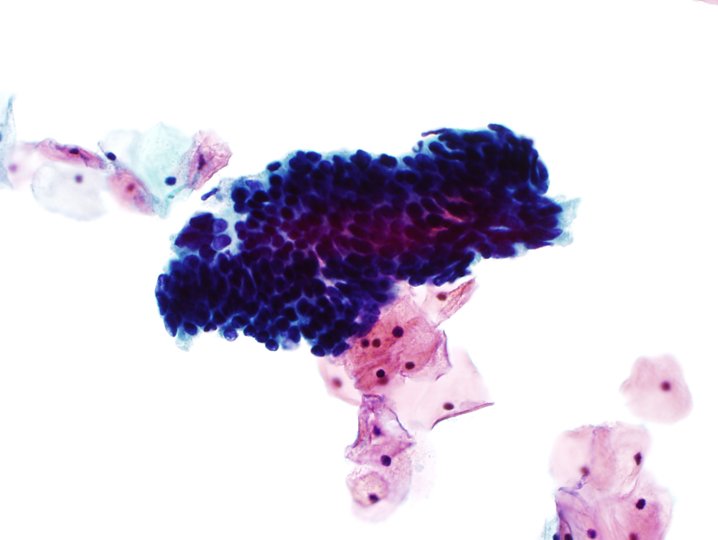

- Atypical endocervical cells, favor neoplastic

- Abnormal cells occur in sheets and strips with nuclear crowding, overlap or pseudostratification

- Rare cell groups with rosettes (gland formations) or feathering

- Nuclei are enlarged and often elongated with some hyperchromasia and coarse chromatin with heterogeneity

- Occasional mitoses or apoptotic debris

- Cell borders may be ill defined

Cytology images

- Endocervical adenocarcinoma in situ (AIS):

- Hyperchromatic nuclei with fine to coarse chromatin

- Nuclear membrane irregularities and notching

- High N:C ratio

- Feathering or rosette formation

A. Atypical glandular cells, favor neoplastic. The image shows endocervical cells with crowding, nuclear overlap, hyperchromasia and focal feathering. Answers B, C and D are incorrect because cytologic features of endometrial adenocarcinoma, HSIL and tubal metaplasia are not seen.